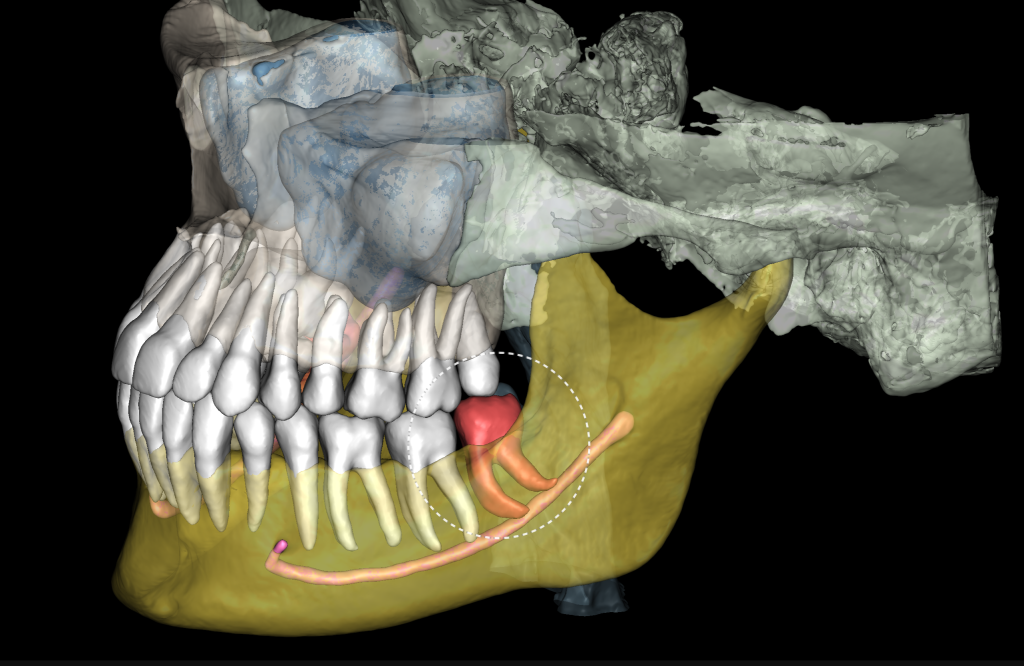

3D реконструкция КЛКЛ является удобным модулем для определения степени сложности предстоящей хирургической манипуляции

А также инструментом визуализации при общении с пациентом

«Отчет по третьим молярам», созданный ИИ Diagnocat — это инструмент, который проводит точный трейсинг нижнечелюстного канала

И выстраивает оптимальную визуализацию в трех плоскостях и помогает врачу оценить расстояние до нижнечелюстного канала